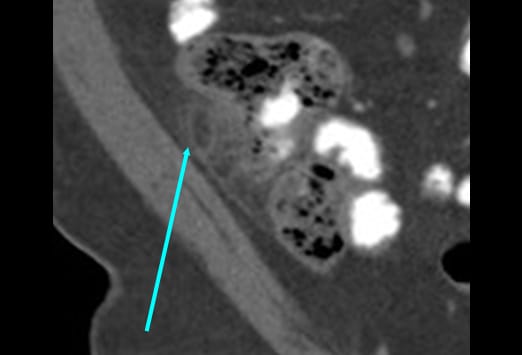

Die Abbildung auf der linken Seite zeigt eine einfache Appendizitis. Hier ist eine Verbreiterung und ein Ödem der Appendix zu sehen, mit einer erhöhten Kontrastmittelaufnahme der Appendixwand (blauer Pfeil) und einer geringen umgebenden Entzündungsreaktion. Beim Fortschreiten einer Appendizitis kommt es von der einfachen Form und einer nachfolgenden gangränösen Veränderung schließlich zur Perforation. Nach der initialen Obstruktion des Lumens kann es zu einer verminderten Perfusion kommen. Das Bild auf der rechten Seite zeigt eine gangränöse Appendizitis, bei welcher es zu einer Zunahme und einer Infiltration in das Mesenterium gekommen ist. Ein Appendikolith (gelber Pfeil) kommt ebenfalls zur Darstellung.